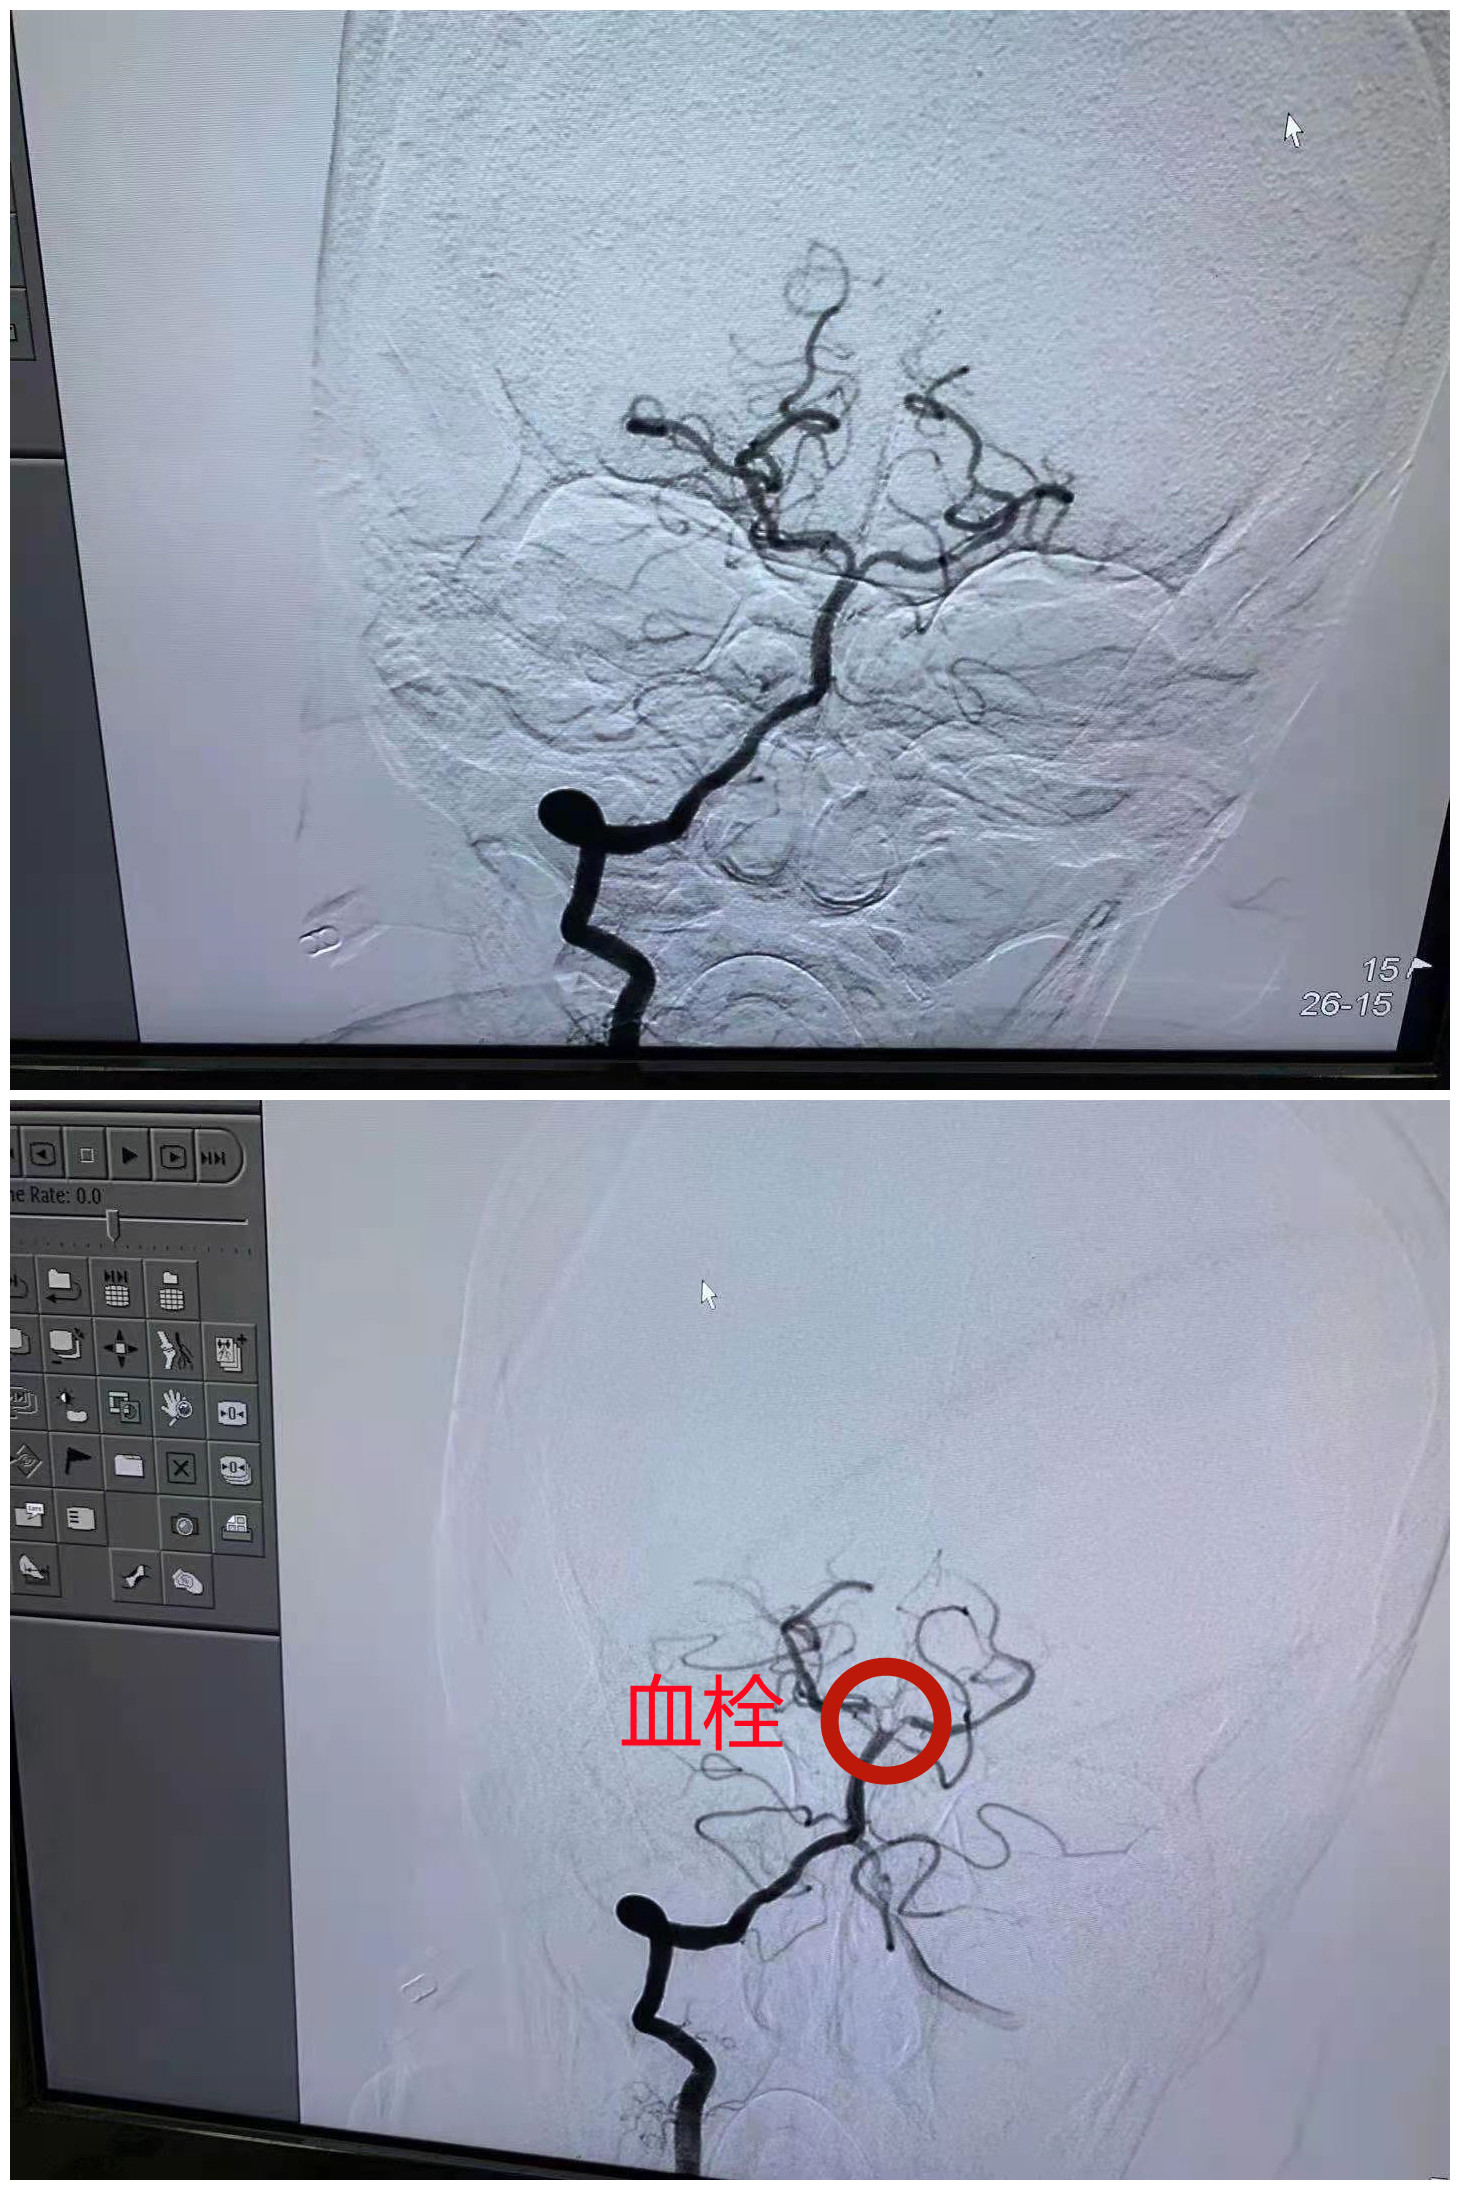

多学科协作完美取栓

根据电话描述急诊科判断王奶奶是一名高度疑似脑卒中患者,于是在第一时间启动“绿色通道”,并通知院内卒中团队一键启动。影像科为王奶奶优先进行了CT及核磁共振检查后直接运往神经重症医学科。神经内科医生快速评估病人情况后决定实行取栓方案,重症医学科与麻醉科开始为病人清理气道,同时介入室团队迅速做好取栓准备工作,马上为王奶奶实施了紧急取栓手术。

在急诊科、神经内科、介入室、手术室、影像科、神经重症医学科、麻醉科团队的无缝衔接下,王奶奶的血栓一次就被完美取出。